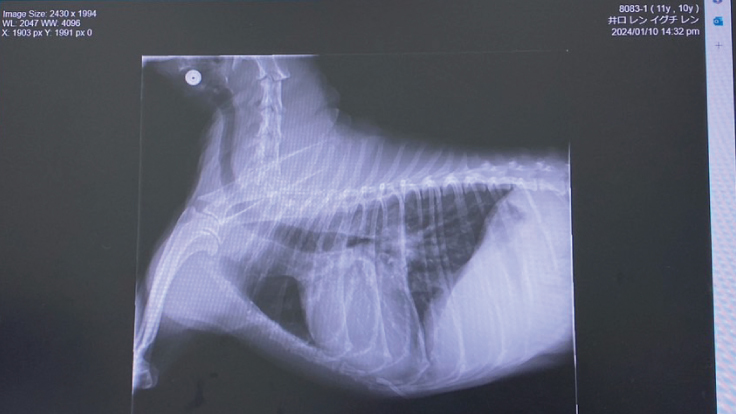

≪僧帽弁閉鎖不全症とは?≫

心臓内の弁膜に病変が起こり、うまく閉じなくなる事で心臓の血流が悪くなる(逆流)が起こる病気です。

この病気は通常ゆっくりと進行して弁膜を支えている腱が切れていくため徐々に逆流量が増え、結果と

して心臓は徐々に肥大し肺に水が溜まるのが肺水腫です。

心臓が負担に耐えられなくなると心不全を引き起こします。一般的に認められる症状は咳、疲れやすい

呼吸困難、失神などで日常生活に支障をきたし生命を脅かす事もあります。

≪肺水腫とは?≫

肺は酸素と二酸化炭素を交換して体内に酸素を取り込む働きをしています。

肺水腫は肺に水が溜まる状態のことです。命を落とす事もある緊急性の高い病気です。

心臓内の弁膜が正常に閉じていないことで

血流が逆流してします。

※動物病院にて掲載の許諾を得ております。

レンの僧帽弁閉鎖不全症は、重度のステージCです。